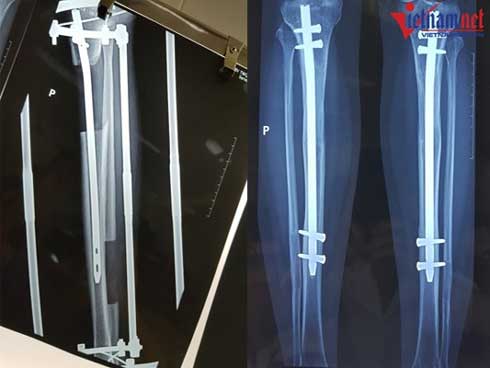

Tuy nhiên từ năm 2010 đến nay, BV 108 cải tiến kĩ thuật, đặt chiếc đinh dài trong ống tủy xương trước khi cắt, giảm số đinh xuyên qua xương chỉ còn 4 đinh và thời gian nằm tại giường chỉ còn 2-3 tháng. Nhờ có đinh cố định, xương khi liền sẽ không bị chệch.

Sau khi đóng đinh vào xương chày, vòng cung phía trên liên kết với 2 đinh Kirschner 2 mm được xuyên chéo nhau ở phần sau của đầu trên xương chày, cách khe khớp gối 2 cm, trên đầu đinh nội tủy khoảng 2 - 3mm.

Vòng cung phía dưới liên kết với 2 đinh Kirschner đường kính 2 mm được xuyên chéo nhau ở đầu dưới xương chày phía trên khe khớp 2cm và nằm phía dưới đinh nội tủy. Các đinh Kirschner được căng bằng dụng cụ căng đinh.

Hai vòng khung trên và dưới được liên kết với nhau bằng 3 thanh liên kết có ren ngược chiều, điều chỉnh độ dãn của xương.

Một chiếc đinh dài được đặt trong lòng ống tủy (trái) và bác sĩ sẽ bắt chốt 2 đầu đinh lại sau khi đạt chiều cao mong muốn

Khi đạt đến chiều cao mong muốn, bác sĩ sẽ bắt chốt 2 đinh lại với nhau và tháo bỏ khung ngoài. Bệnh nhân sẽ được bó bột, sau đó bắt đầu tập đi dưới sự trợ giúp của khung hoặc nạng.